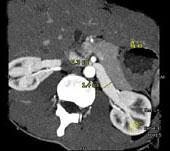

问题 女 ,24 岁,发作性肉眼血尿1 年,实验室检查:尿蛋白 (- +)、红细胞1 2/HP,尿蛋白直立试验 (+),CT扫描如图,下列说法正确的是 ( )

选项 A、左侧肠系膜上动脉与腹主动脉夹角增大 B、考虑为左肾静脉胡桃夹综合征 C、左肾静脉走行至肠系膜上动脉与腹主动脉间变细,近左肾处扩张 D、左侧肠系膜上动脉与腹主动脉夹角变小 E、双肾大小形态正常

答案 BCDE